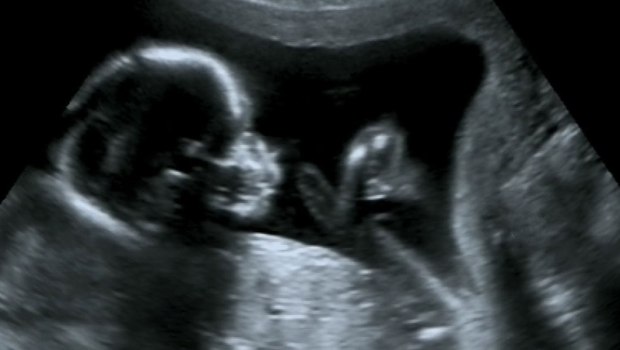

“El tejido fetal utilizado en la investigación se obtiene a partir de abortos electivos”, dice el Servicio de Investigación del Congreso .

Según el reportaje de CNSNews, en 2016, la Universidad de Harvard brindó al Panel de Investigaciones Selectas sobre Vidas Infantiles del Comité de Energía y Comercio de la Cámara de Representantes, un documento de antecedentes que explica que los ratones con sistemas inmunes humanos “están diseñados para esta condición solo mediante el uso de material fetal humano” y que este material solo puede provenir de bebés abortados y no de abortos espontáneos.

Debido a que no sería capaz de crear sus “ratones humanizados” sin tejido fresco extraído de bebés abortados, la FDA también tiene interés en la continuación de los abortos legalizados en una etapa del desarrollo fetal cuando se puede recuperar el tejido necesario para crear estos ratones. del bebé abortado.